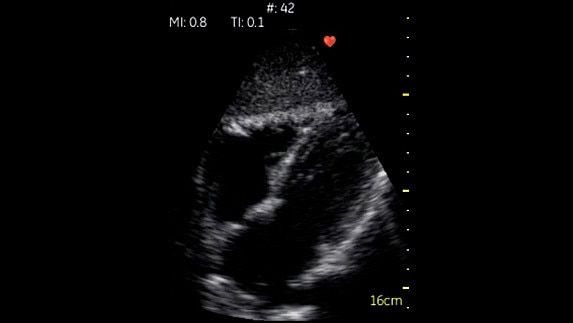

Phased Cardiac